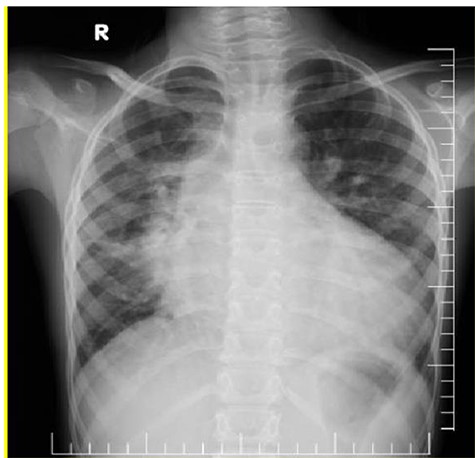

(A) Chest X-ray showed prominent pulmonary vascular marking, atelectasis in the right lung and cardiomegaly with a widening mediastinum. (B and C) Echocardiography: short-axis view revealed VSD (B) and long-axis view showed ascending aortic aneurysm (C).

A 15-year-old male presented to our hospital with a history of shortness of breath and cough for 2 months. The patient was one of five children with no family history of CHD. His growth had been normal and there was no history of recurrent or chronic illness during his life. On examination, his blood pressure was 120/70, SpO2 was 97%, digital clubbing was present, a parasternal heave was noted in the left second intercostal space and a systolic murmur was present. All his blood tests were normal. Electrocardiogram was normal and a chest radiograph showed prominent pulmonary vascular markings, atelectasis in the right lung and cardiomegaly with a widening of the mediastinum due to a large aortic shadow (Fig. 1).